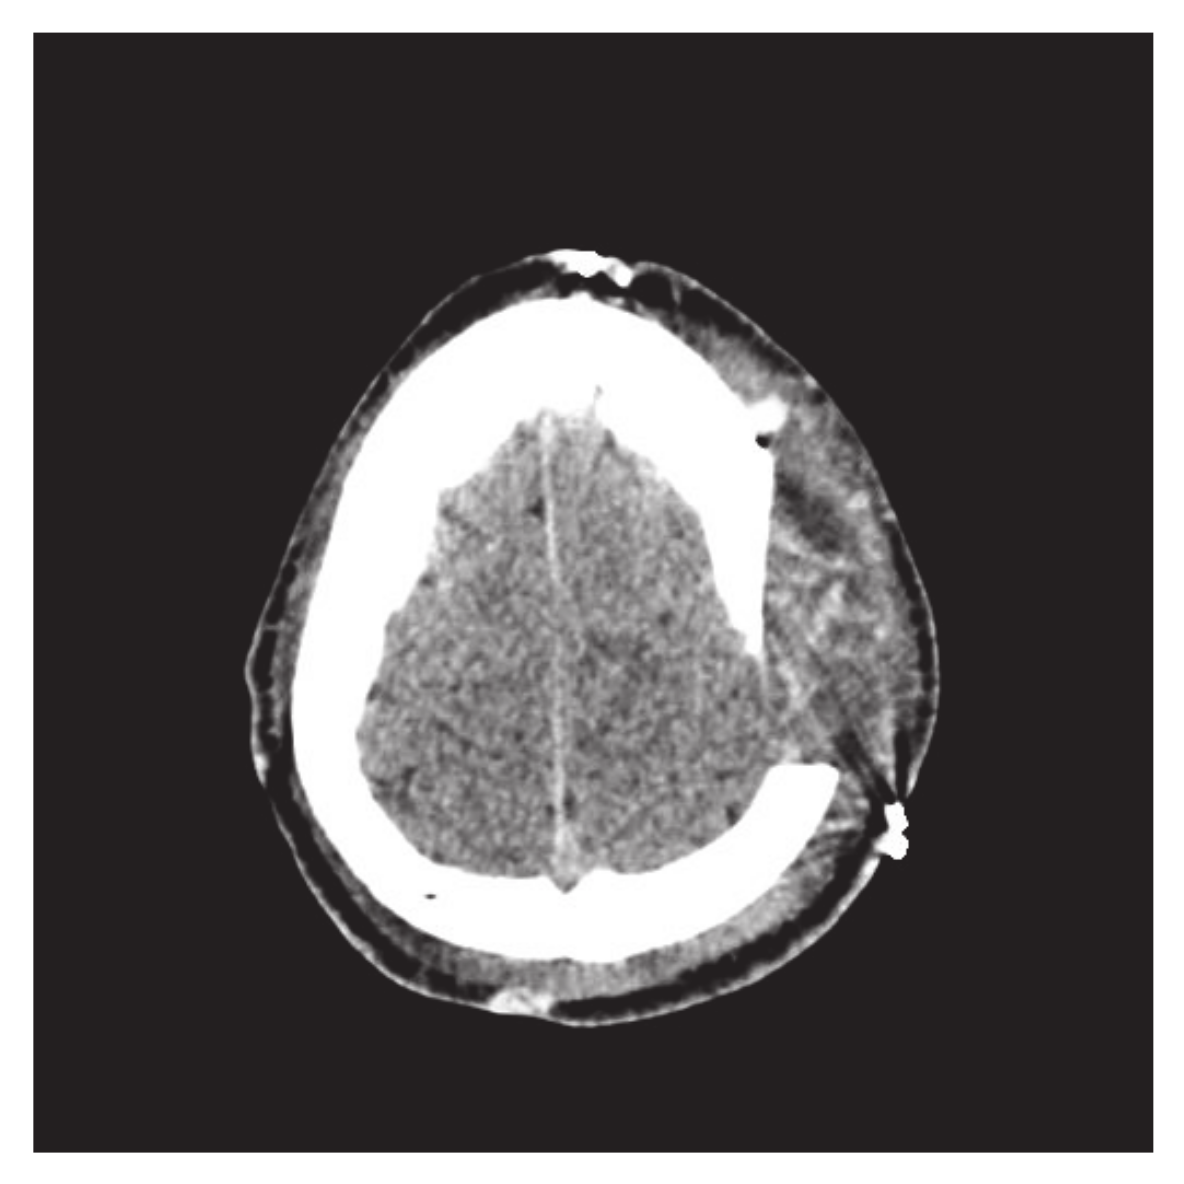

- Majeed, A.; Abbas, M.; Miura, K.T.; Kamran, M.; Nazir, T. Surface modeling from 2D contours with an application to craniofacial fracture construction. Mathematics 2020, 8, 1246. [Google Scholar] [CrossRef]

- Majeed, A.; Rafique, M.; Abdullah, J.Y.; Rajion, Z.A. NURBS curves with the application of multiple bones fracture reconstruction. Appl. Math. Comput. 2017, 315, 70–84. [Google Scholar] [CrossRef]

| 1 | Technical staff | Refs. [2,3] used CAD/CAM process for craniofacial fracture reconstruction. It required technical staff/tools, which causes low efficiency and high cost | In this method, no need for staff/tools, reconstruction is based on patient CT scan DICOM data |

| 2 | Mirroring Method | Ref. [5] constructed the cranial part using the mirroring method. This method is not suitable for the patient with multiple bone fractures | The scheme based on spline functions is independent of mirroring and will work for any type of fractures. |

| 3 | Reference skull | Refs. [7,8] used adaptive deformation method for reconstruction. This scheme is dependent on reference skull | There is no need to take the reference skull using this method and reconstruction is based on CT scan data. |